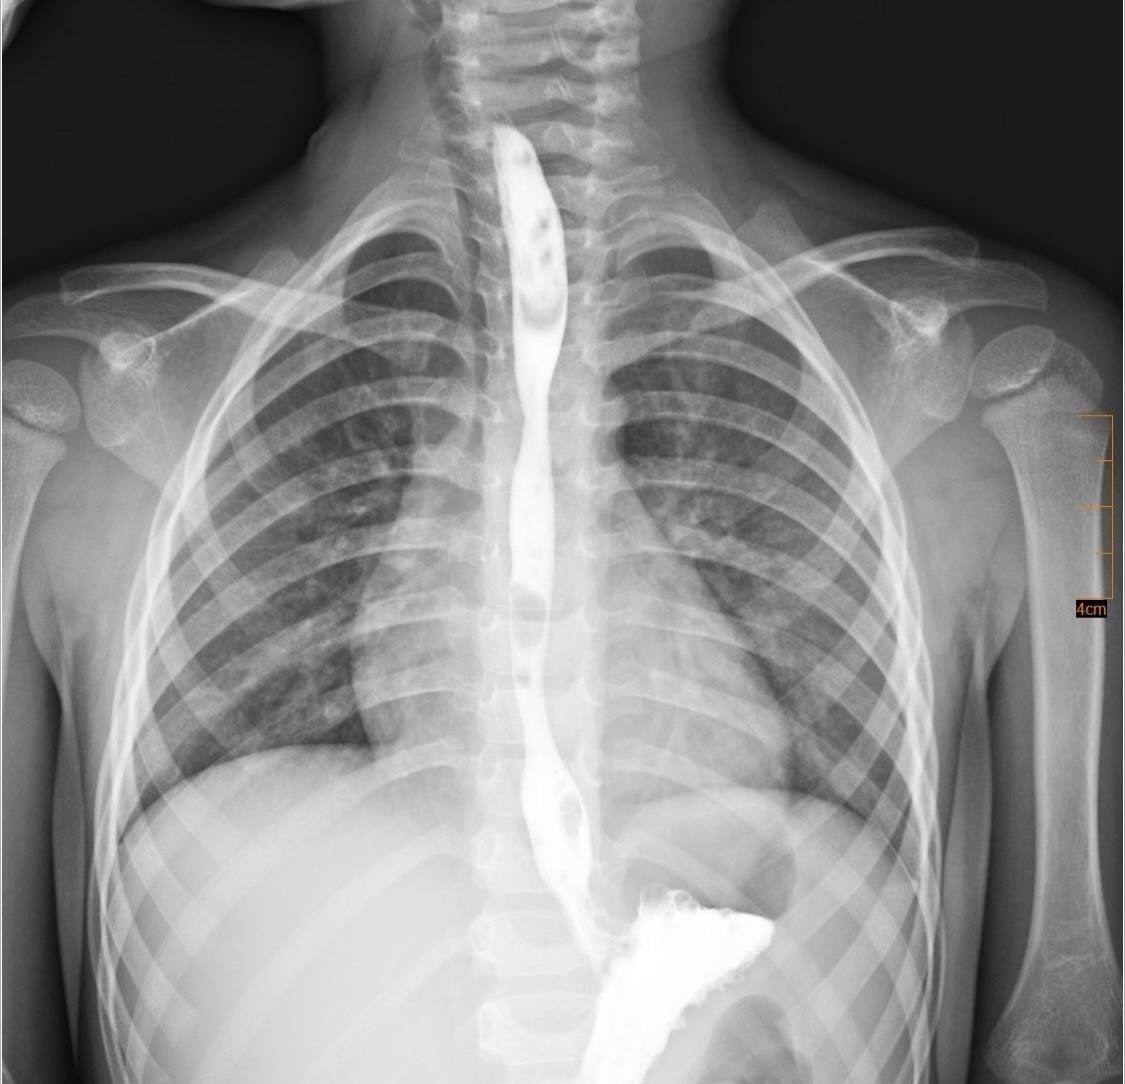

Со временем у мальчика сформировался критический стеноз — резкое сужение пищевода, что полностью сделало невозможным прием пищи через рот.

После консультаций мультидисциплинарная команда решила провести серию малоинвазивных процедур — баллонных дилатаций, во время которых суженный участок постепенно расширяли эндоскопически, без разрезов.

Рентгенобследование пищевода после выздоровления мальчика